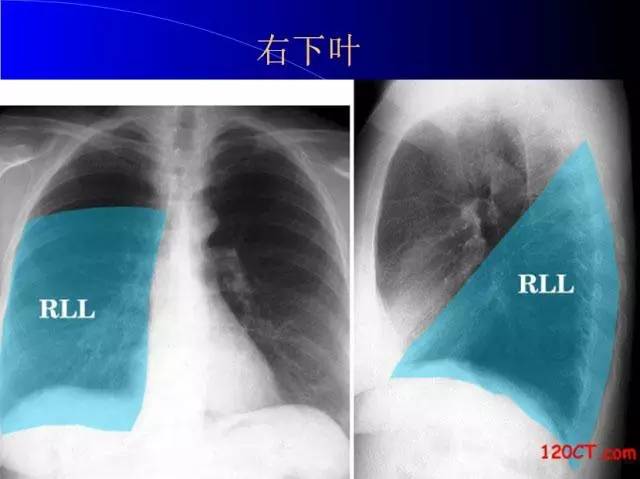

肺部基础X片及CT片解读